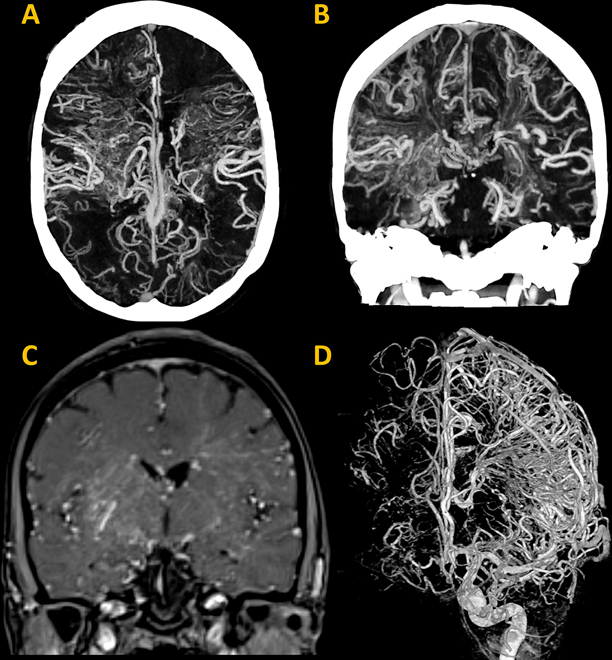

The second runner-up of 2024 Top Images in Radiology is “Diffuse Cerebral Proliferative Angiopathy,” by Dhairya A. Lakhani and SoHyun Boo. This article depicts the case of a 47-year-old woman presenting with transient episodes of left facial numbness, anomic aphasia, and left facial weakness. Head CT angiography and MRI revealed a diffuse network of vessels involving both cerebral hemispheres, with intermingled normal brain parenchyma. Angiography demonstrated diffuse pooling of contrast medium in the nidus with capillary ectasia, without dominant feeding, early draining vessels, or intracranial large-vessel stenosis. The final diagnosis was cerebral proliferative angiopathy, an extremely rare progressive vascular disease with fewer than 100 reported cases.